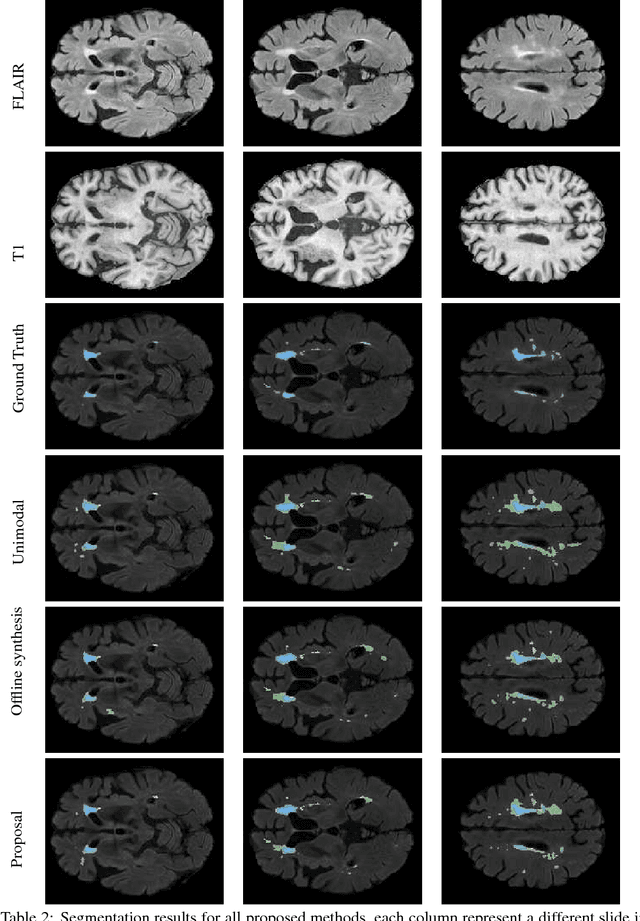

Abstract:Segmenting vascular pathologies such as white matter lesions in Brain magnetic resonance images (MRIs) require acquisition of multiple sequences such as T1-weighted (T1-w) --on which lesions appear hypointense-- and fluid attenuated inversion recovery (FLAIR) sequence --where lesions appear hyperintense--. However, most of the existing retrospective datasets do not consist of FLAIR sequences. Existing missing modality imputation methods separate the process of imputation, and the process of segmentation. In this paper, we propose a method to link both modality imputation and segmentation using convolutional neural networks. We show that by jointly optimizing the imputation network and the segmentation network, the method not only produces more realistic synthetic FLAIR images from T1-w images, but also improves the segmentation of WMH from T1-w images only.